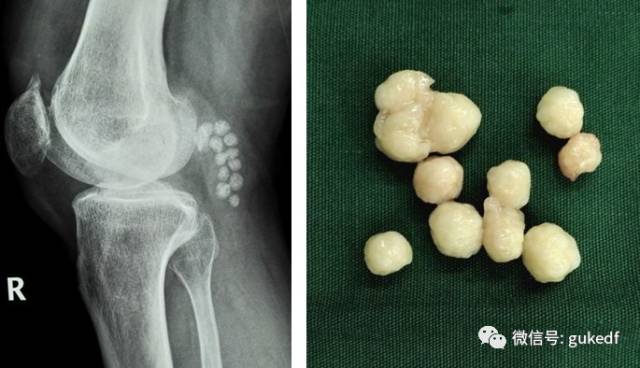

8.对于关节内软骨剥脱形成游离体,以及半月板撕裂产生卡压、交锁症状的患者可以考虑膝关节镜下清理游离体(图4)和增生的滑膜组织,或镜下微创缝合损伤撕裂的半月板(图5)。前(后)交叉韧带断裂的可行关节镜下的韧带重建手术(图6)。

图4.膝关节镜清理游离体